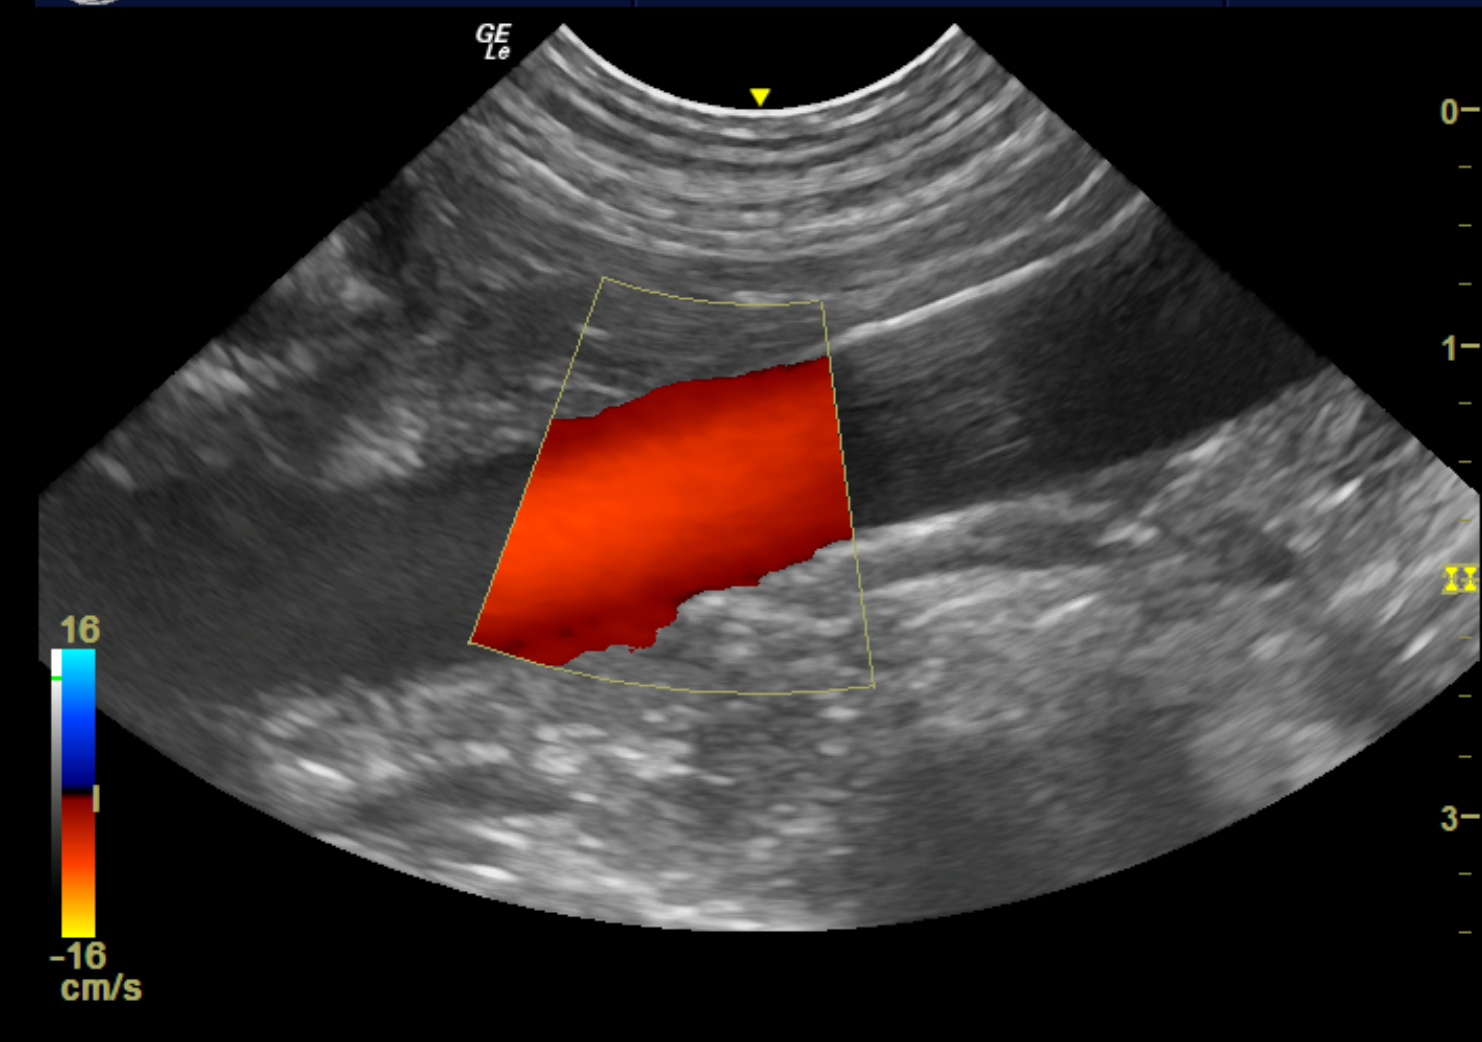

Abdominal ultrasound – complete assessment of the intra-abdominal organs

Thoracic ultrasound – evaluation of mediastinal masses, pleural lesions, or peripheral pulmonary masses

Cervical ultrasound – assessment of thyroid and parathyroid gland or evaluation of abnormalities or masses in this region (including salivary gland, mandibular and medial retropharyngeal lymph nodes, larynx)

Ocular ultrasound – for evaluation of primary intraocular neoplasia, retinal detachment, or retrobulbar space disease

Pregnancy ultrasound – confirmation, presence and estimated rate of fetal heartbeats